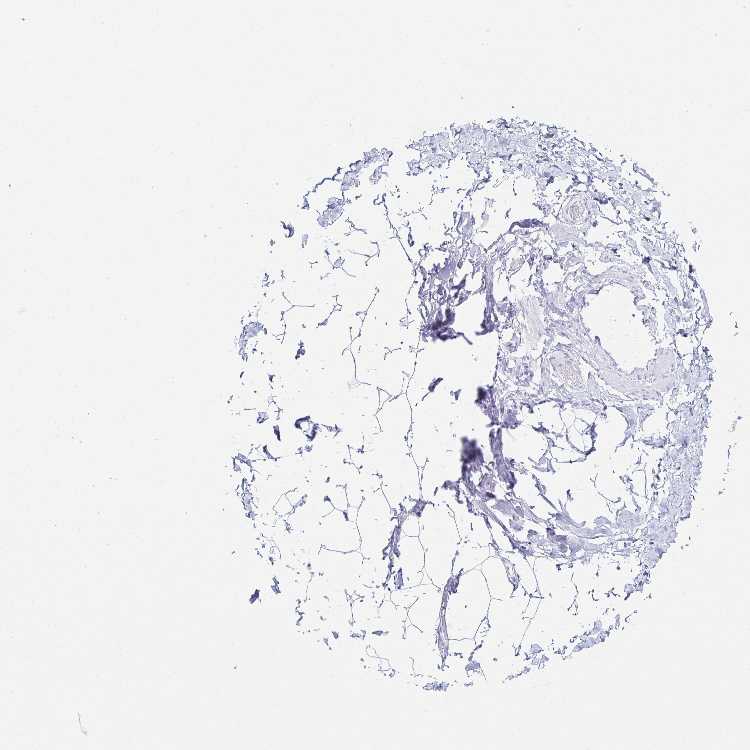

PRKCG